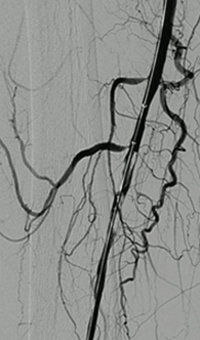

Venous thrombosis extending from popliteal to external iliac vein

Extensive DVT of the right common femoral and external iliac was treated with the 8 F AngioJet™ ZelanteDVT™ catheter.

Patient history

73 year old with 1-week old right leg swelling and pain.  Started on anticoagulation and discharged.

Consult confirmed extensive DVT from popliteal extending into external iliac vein.

Procedural steps

• Power Pulse ( tPA 10 mg in 50 cc)

• Patient put on 2-hour lytic catheter drip in holding area

• Thrombectomy performed with 8F ZelanteDVT catheter

• Directional ability of ZelanteDVT allowed targeting of residual thrombus in Popliteal and Superficial Femoral Vein Post Venography shows complete resolution of thrombus

xray of occlusive thrombus extending into the iliac vein.

Occlusive thrombus extending into the iliac vein

xray of femoral vein pre-treatment.

Femoral vein pre-treatment

xray image of Iliac vein post-ZelanteDVT.

Iliac vein post-ZelanteDVT

xray image of liac vein post-PTA & stent.

Iliac vein post-PTA & stent

Femoral vein post-ZelanteDVT.

Femoral vein post-ZelanteDVT

Images courtesy of Jeffrey Y. Wang, MD FACS, Vascular Surgeon; Horizon Vascular Specialist, Maryland.  November, 2015